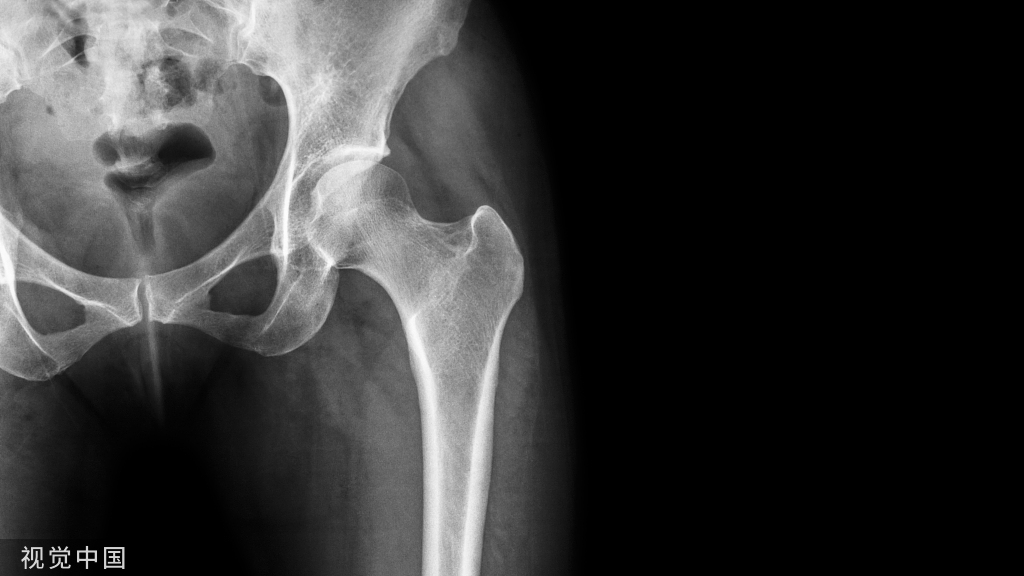

“骨质疏松症”的诊断分为临床诊断和仪器诊断。如果病人已经发生“脆性骨折”,即在轻微外力的作用下就发生骨折,如咳嗽两声就导致肋骨的骨折,下楼梯仅仅踩空一下没有摔倒就导致小腿骨折,这种情况不做骨密度检查就可以直接诊断为骨质疏松症。但是对于没有发生骨折的病人,则需要借助骨密度检查来诊断骨质疏松症。检查方法是用双能X线骨密度仪检查腰椎和股骨颈的骨密度。

诊断标准:T≥-1.0SD属正常;-2.5SD<T<-1.0SD为骨量减少;T≤-2.5SD为骨质疏松。达到骨质疏松诊断标准同时伴有一处或多处骨折时为“严重骨质疏松”。